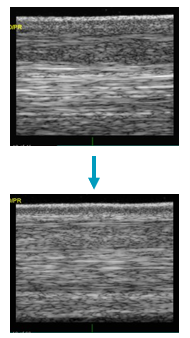

What collagen type is present in healthy tendon?

A

Collagen type I

What collagen type is present in tendon after injury?

Collagen type III